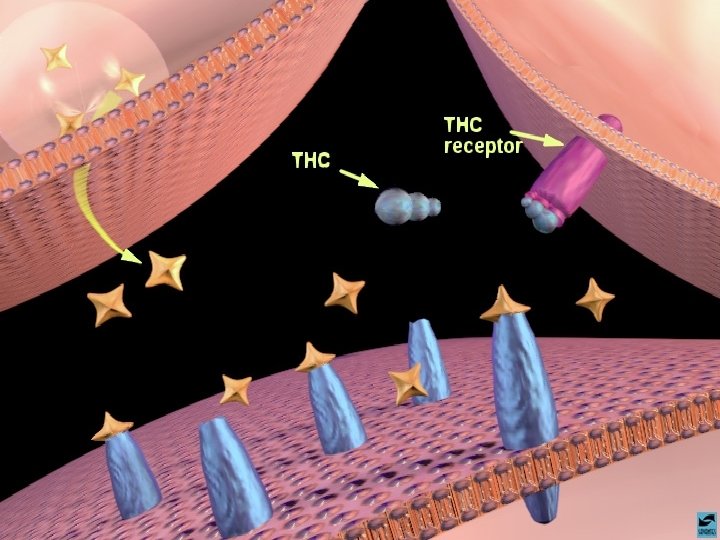

MACONHA TETRAHIDRO CANABINOL EFEITOS CEREBRAIS 1 - DISTRIBUI-SE RAPIDAMENTE POR TODO O CÉREBRO 2 - TEM AFINIDADE COM O RECEPTOR FORMADO AMANDAMIDA, QUE EXISTE NO HIPOCAMPO, TRONCO CEREBRAL E TRATO PÁLIDO 3 - AGE COMO NEUROMODULADOR ALTERANDO A PRODUÇÃO DE UM SEGUNDO MENSAGEIRO REGULADO POR OUTRO NEUROTRANSMISSOR